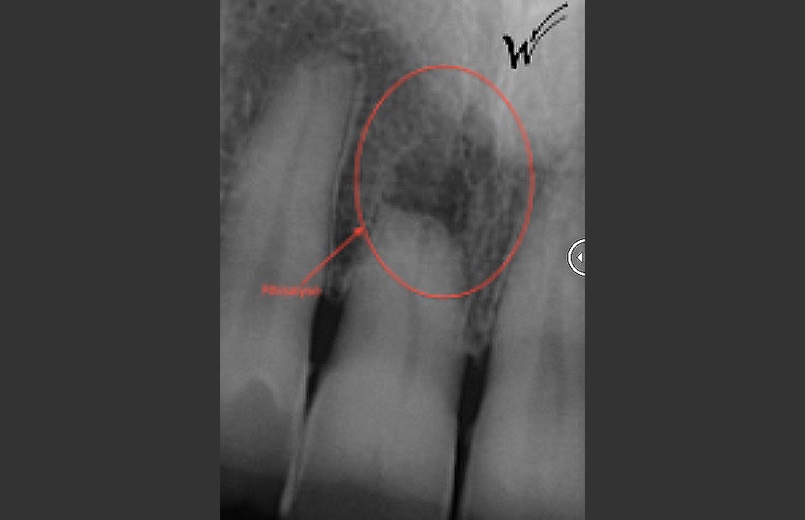

En raison de problèmes de rhizalyse, une résorption pathologique de la racine, ainsi que d’une infection, l’incisive centrale du patient a été extraite.

Lors de cette extraction, des biomatériaux (substituts osseux) ont été utilisés pour combler l’alvéole vidée. Il était également essentiel de réparer ou de renforcer la paroi externe de cette alvéole pour prévenir sa résorption. La finesse de cette paroi autour de la racine naturelle de l’incisive (quelques dixièmes de millimètres) ne permettait pas la pose d’un implant seul, compte tenu du vieillissement des tissus environnants et de l’importance de l’esthétique à ce niveau.

L’implant a été positionné dans l’alvéole, aligné avec la racine. À ce stade, un guide chirurgical peut s’avérer extrêmement utile, en particulier pour éviter d’éventuels obstacles anatomiques, tels que des paquets vasculo-nerveux situés dans le trou rétro-incisif.